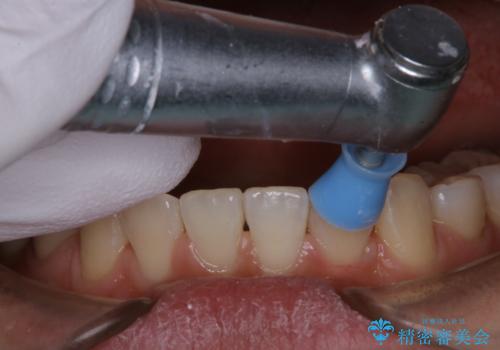

- 当院でのインビザライン矯正治療が終了し、メンテナンスにいらしている方です。PMTC30分コースを行いました。

ご自身での歯ブラシ・セルフケアを行うと同時に、定期的なクリーニング(PMTC)を行うことで、いつまでも健康な歯を保つことができます。